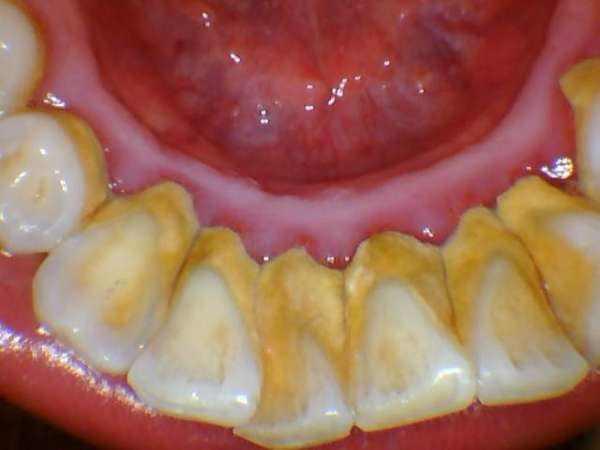

牙結石凡是存在於唾液腺啟齒處的牙齒外表(比方:下顎前牙的舌側外表,上顎后牙的頰側外表)和牙齒的頸部,還有口腔粘膜活動不到的牙齒外表等處。牙結石開始時是軟軟的,會因逐步的鈣化而變硬。它是由75%的磷酸鈣,15-25%的水、有機物、磷酸錳、礦酸鈣及微量的鉀、鈉、鐵所組成。並呈現出黃色、棕色、或許玄色。